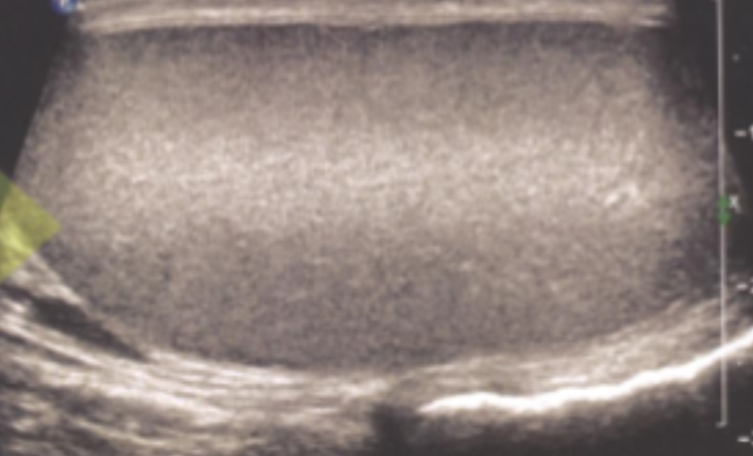

Slice (Section) Thickness

AKA Partial Volume Filling

Beam is too thick in the elevation plane

Gives the appearance of debris in an echo-free structure